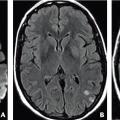

En effet, dans 5 % des cas, le déficit neurologique transitoire est dû à une hémorragie intracérébrale (fig. 1a, malformation vasculaire : cavernome) ou à d’autres maladies à risque hémorragique (fig. 1b, angiopathie amyloïde cérébrale).

Les principaux sont l’hypoglycémie, la crise épileptique partielle et l’aura migraineuse (tableau 1). L’examen clinique peut contribuer à les éliminer. L’IRM encéphalique (encadré 1) est un examen précieux pour poser le diagnotic (fig. 1).

L’IRM encéphalique est préférable à la tomo- densitométrie (TDM) parce que, contrairement à celle-ci, elle montre les lésions hémorragiques anciennes de petite taille.

La séquence de diffusion est indispensable ainsi que celle dite T2*-écho de gradient (encadré 1).

Séquence de diffusion (DWI, Diffusion Weighted Imaging) : l’hypersignal traduit le ralentissement de la mobilité des molécules d’eau secondaire aux lésions ischémiques avec présence d’un œdème cytotoxique dès les premières minutes. La cartographie du coefficient apparent de diffusion (ADC, Apparent Diffusion Coefficient) permet une évaluation quantitative du mouvement, diminué (restriction), en cas d’ischémie.

Séquence T2*-écho de gradient : l’hyposignal traduit la présence d’hémosidérine, produit de dégradation de l’hémoglobine. Cette séquence permet la mise en évidence d’une hémorragie intracrânienne.

Autres séquences : FLAIR (évaluation morphologique du parenchyme cérébral) et ToF (imagerie vasculaire, notamment du polygone de Willis, sans injection de produit de contraste).